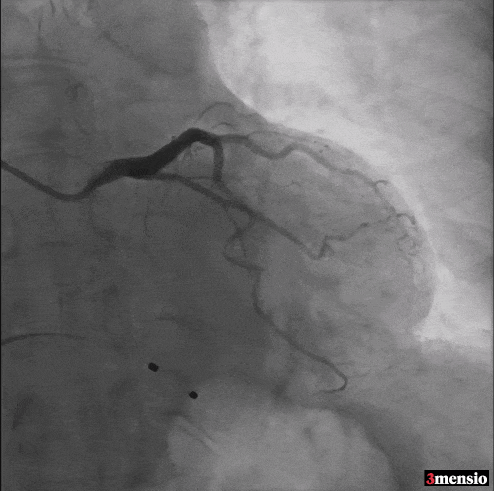

Step 1 冠状动脉造影及右窦中心造影

Step 2 瓣膜定位、释放